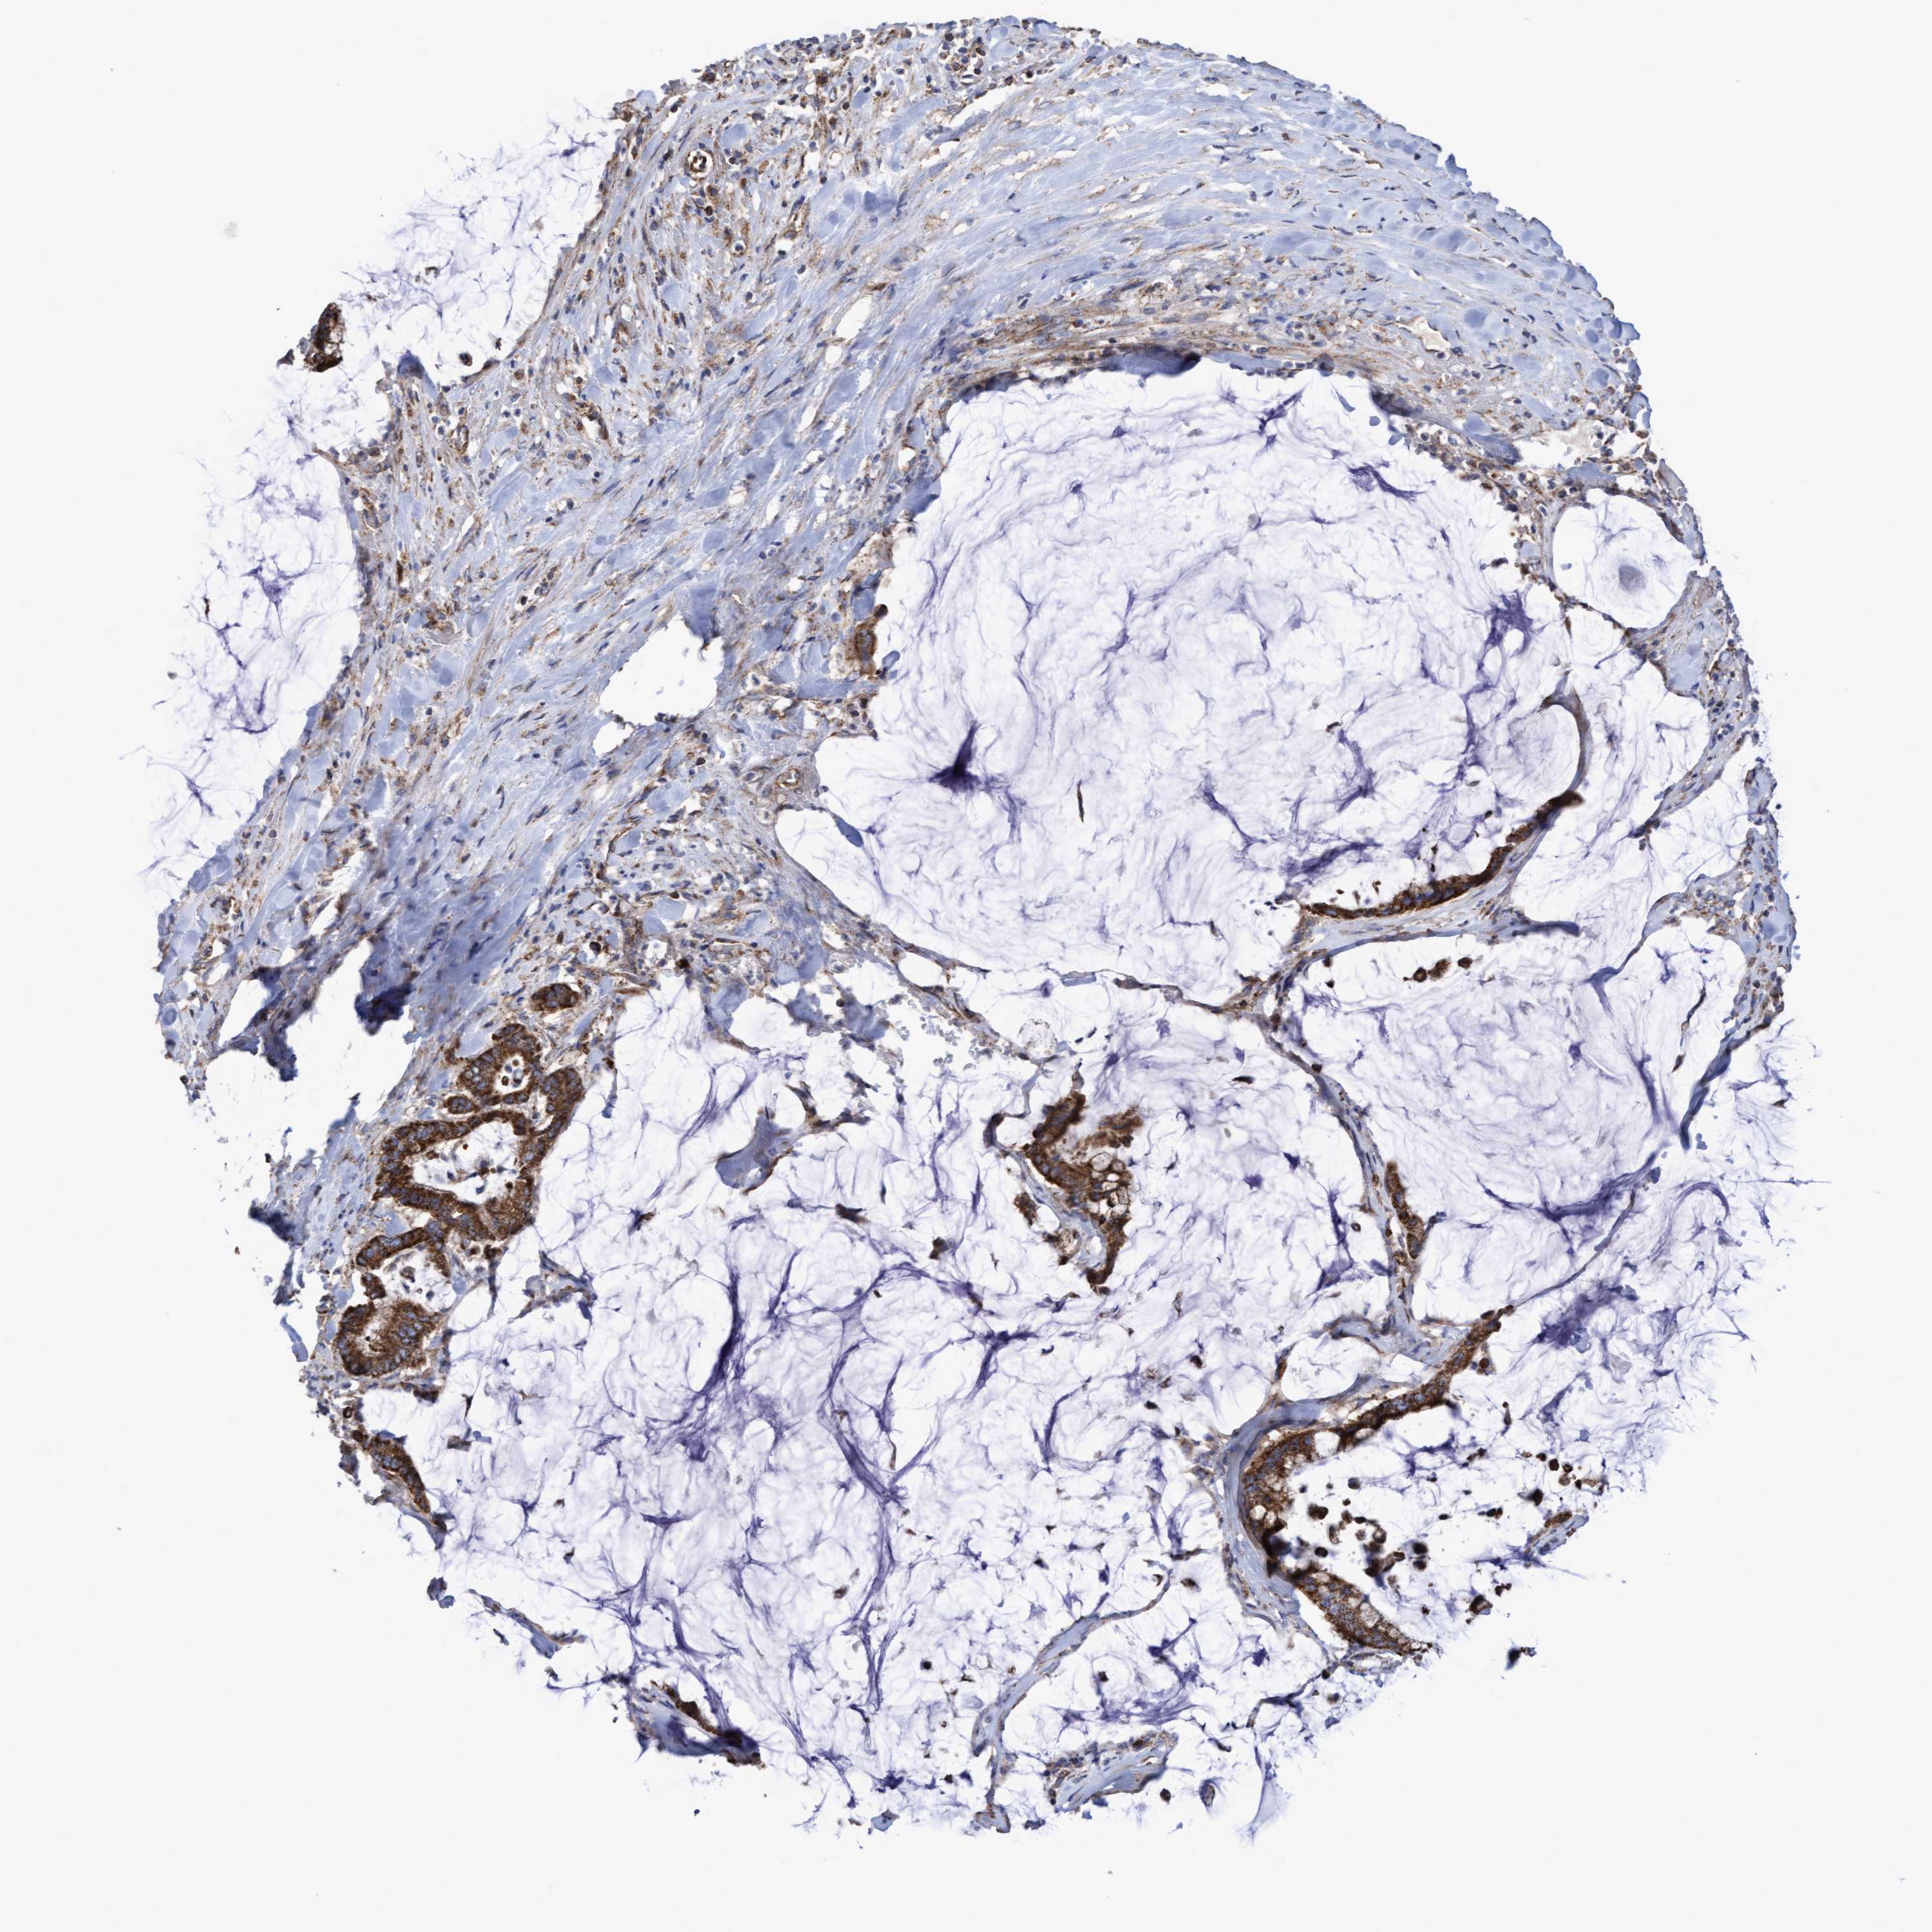

PANCREATIC CANCER - Protein expressioni

A mouse-over function shows sample information and annotation data. Click on an image to view it in a full screen mode. Samples can be filtered based on level of antibody staining by selecting one or several of the following categories: high, medium, low and not detected. The assay and annotation is described here.

Note that samples used for immunohistochemistry by the Human Protein Atlas do not correspond to samples in the TCGA dataset.

Antibody stainingi

Antibody staining in the annotated cell types in the current human tissue is reported as not detected, low, medium, or high, based on conventional immunohistochemistry profiling in selected tissues. This score is based on the combination of the staining intensity and fraction of stained cells.

Each image is clickable and will lead to virtual microscopy that enables deeper exploration of all samples and also displays staining intensity scores, fraction scores and subcellular localization as well as patient and tissue information for each sample.

Antibody HPA019033

Antibody HPA019167

Staining

High

Medium

Low

Not detected

Intensity

Strong

Moderate

Weak

Negative

Quantity

>75%

75%-25%

<25%

None

Location

Nuclear

Cytoplasmic/membranous

Cytoplasmic/membranous,nuclear

Adenocarcinoma, NOS